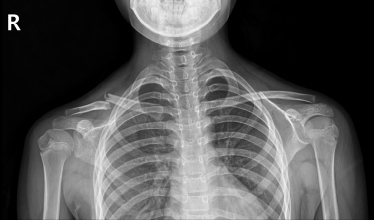

견쇄관절 탈구

2022.10.04

2022.12.27